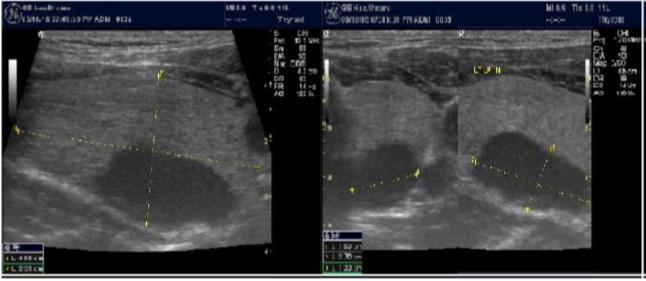

The reported prevalence of nodular thyroid disease depends on the population studied and the methods used to detect nodules 16. Our study population is unique as it is composed entirely of ESKD patients. We also used ultrasound as a method of detecting thyroid abnormalities. In our study the prevalence of thyroid nodular pathology as detected by ultrasound was found to be 57.6% mirror image what reported in the literature as it has been reported that nodules found on ultrasonography suggest a prevalence of 19 to 67%17, 18; and in other publications it has been reported to range from 50% to 70% 7, 8. Figure 3A below shows an Ultrasound detected thyroid nodule.

Figure 3A.Thyroid nodule

Thyroid nodule

High-resolution ultrasonography (USG) is the most accurate and cost-effective method for evaluating and observing thyroid nodules 3. Although there is some overlap between ultrasound appearance of benign and malignant nodules, certain USG features are helpful in differentiating the two. Iso-or hyper-echogenicity of the thyroid nodule in conjunction with a spongiform appearance is the most reliable criterion for benignity of the nodule on gray-scale ultrasound, Figure 4A. Other features like nodule size <1 cm, width > length, presence of hypoechoic or hyperoechoic halo around the nodule, Figure 4A and Figure 4B, caused by fibrous capsule compressing thyroid tissue, and coarse/curvilinear calcification are less specific but may be useful ancillary signs4 ,6.  "Ring down" or "comet-tail" artifact or sign is typical of benign cystic colloid nodule, Figure 520.  Perinodular flow or spoke-and-wheel-like appearance of vessels on color Doppler examination is characteristic of a benign thyroid nodule. However, this flow pattern may also be seen in thyroid malignancy. A complete avascular nodule is very unlikely to be malignant 4.

Figure 4A.isoechoic nodule

isoechoic nodule

Figure 4B.Isoechoic nodule with Hyperechoic rim

Isoechoic nodule with Hyperechoic rim